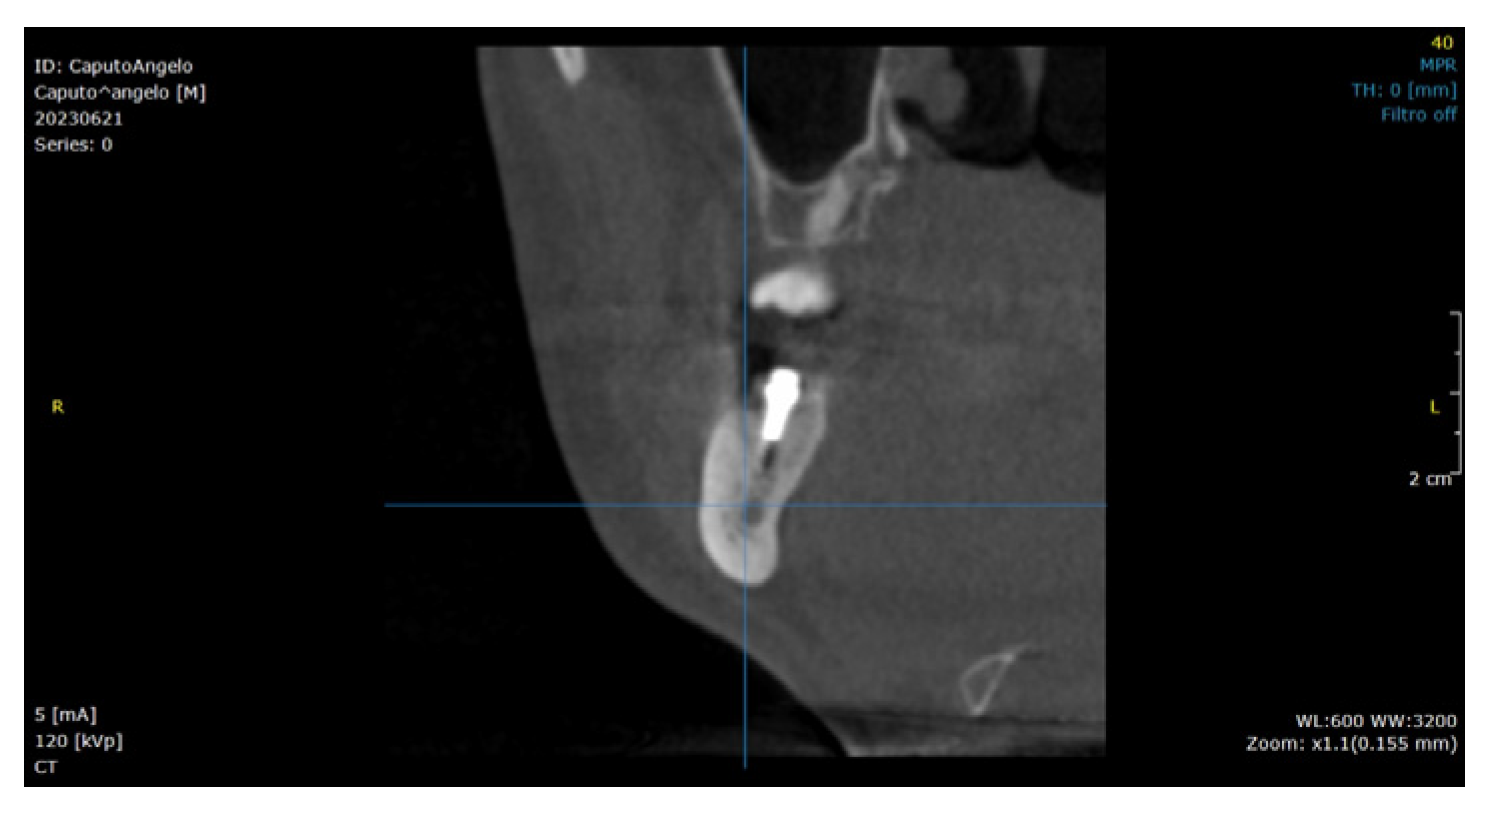

:1. Introduction

2.2. Surgical Technique

3. Results